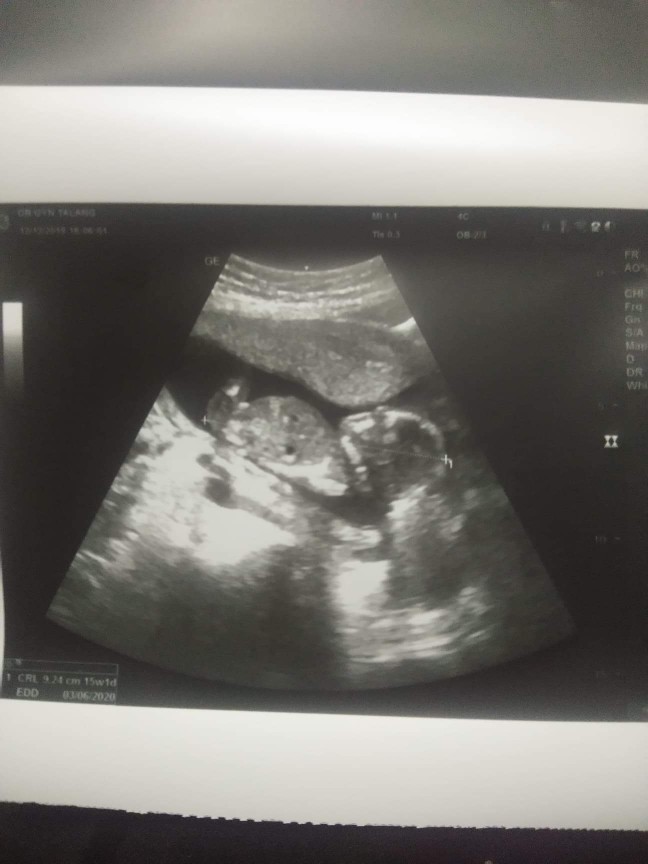

อันนี้ตอน14w+3ค่ะตอนนี้ได้18w+2แล้วค่ะน้องกำลังดิ้นเลยค่ะ